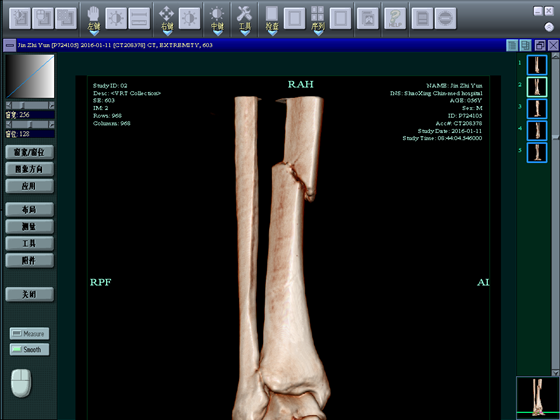

病例2

金**,男,56岁,骑电瓶车时跌倒。

术前